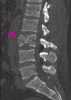

압박골절 시에는 lateral X-ray 검사에서 추체 전방부 높이가 낮아지므로 후만 기형(kyphotic deformity)이 발생합니다. 방출형 골절(burst fracture)은 CT에서 가장 잘 나타납니다. 불안정한 굴곡-신연 손상 시에는 AP, lateral X-ray에서 극돌기 사이의 간격이 벌어집니다. AP view에서 횡돌기 골절이나 불안정한 방출형 골절로 인한 척추경 사이 간격(interpedicular distance)이 넓어짐을 확인할 수 있습니다. 한 추체가 아래 추체에 비해 돌아가 있는 것도 척추 불안정성을 시사합니다. 단순 압박골절 이외에도 어떠한 부상이 있다면 추가적인 영상이 필요할 것입니다.

CT : 흉추/요추 골절(Fractures of the Thoracic or Lumbar spine)